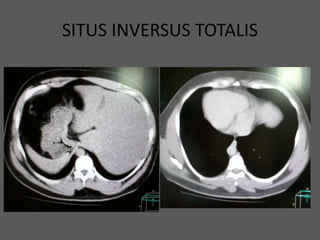

SITUS INVERSUS TOTALIS